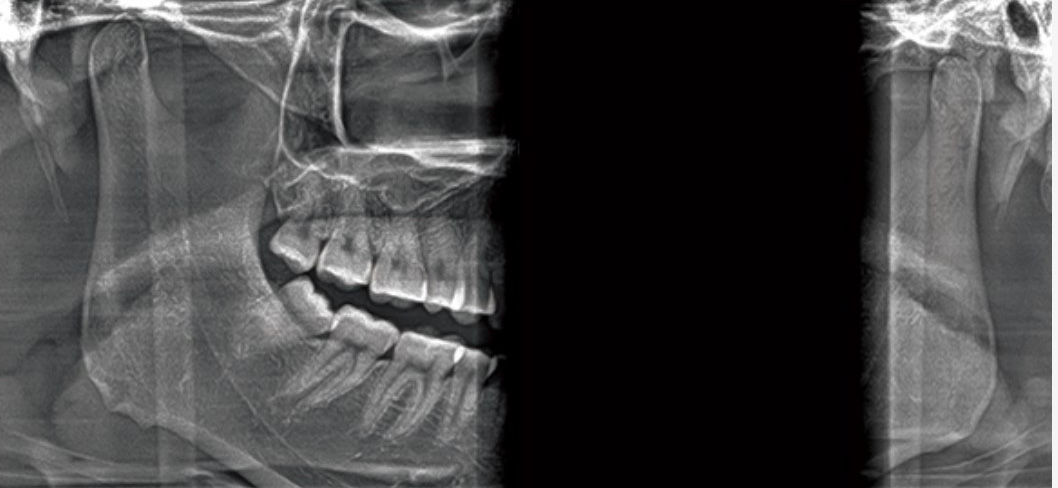

Modo multifuncional lateral/cefálico

Hay cinco modos para elegir: posiciones anteroposterior, lateral, Coriolis, Farenheit y metacarpiana

Diferentes modos: craneal, AP/PA y carpiano

ATM bilateral

Con un gran campo de visión de 14*10, el modo ATM facilita el diagnóstico médico de enfermedades de la articulación temporomandibular.